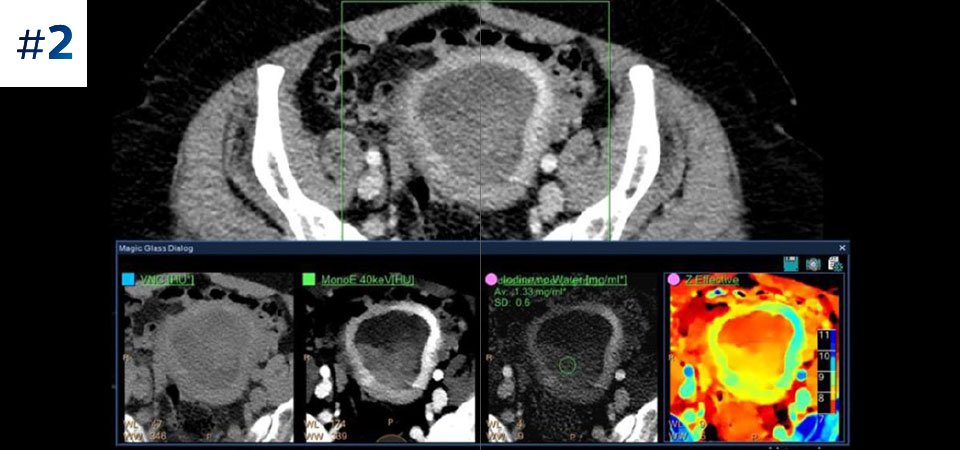

Scan as usual A single scan for fast, low-dose conventional and spectral data for every patient, every time.

Always available 100% spectral, 100% of the time for results that are always available on-demand, even retrospectively.